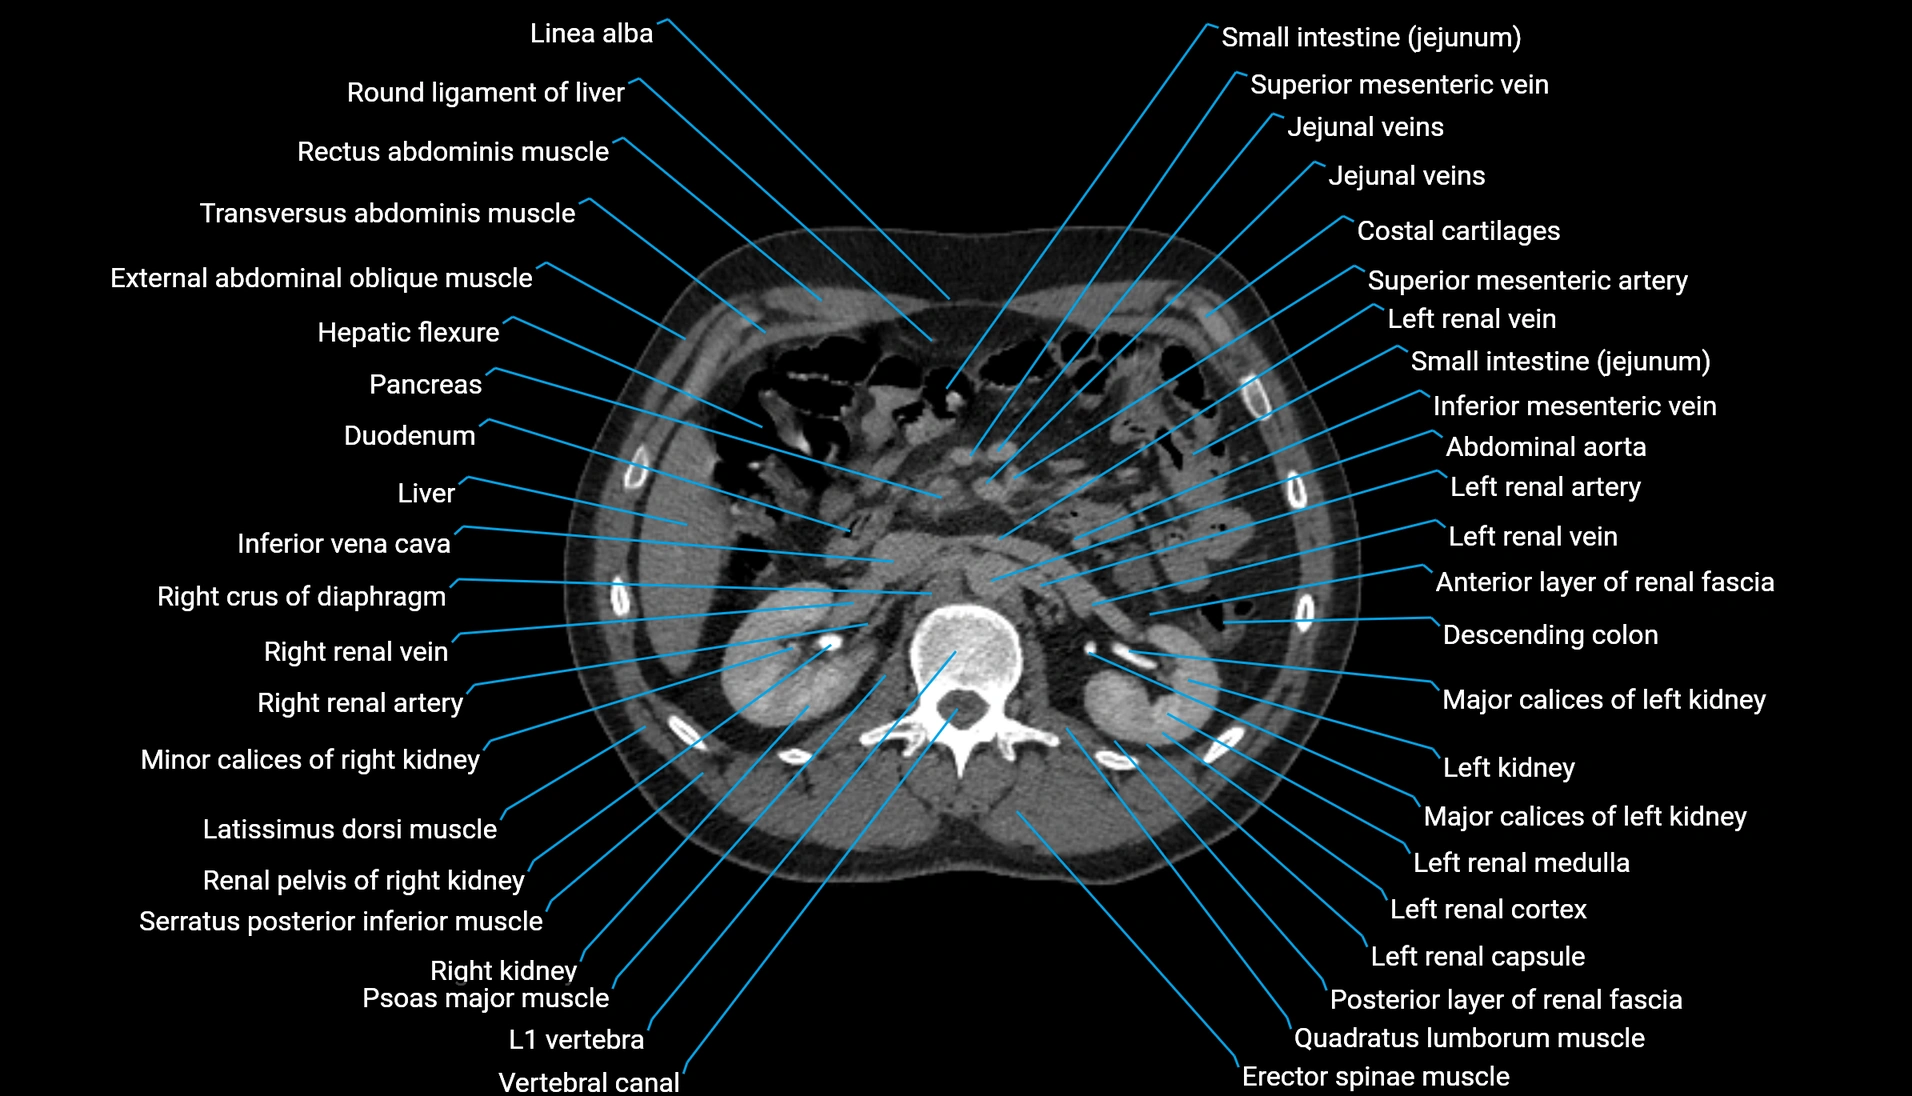

CT Appearance

Non-contrast CT:

-

Demonstrates cortical bone of acetabular rim in excellent detail

Detects fractures, dysplasia, retroversion, or bony overcoverage (pincer impingement)

3D reconstructions used in preoperative hip surgery planning

CT VRT 3D image

CT image